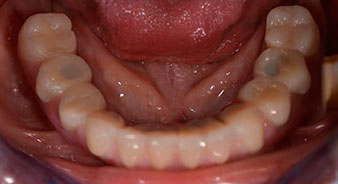

Après ostéointégration, l'empreinte finale des implants a été effectuée et la prothèse finale a été fabriquée en conséquence (Fig. 19 et 20). À cette étape, le praticien et le patient ont pu décider ensemble d'utiliser une facette dentaire en céramique ou en acrylique et une armature en zircone ou en métal. Dans ce cas, l'équipe du Dr Pascu a opté pour une facette dentaire en acrylique en raison du pronostic incertain de la denture maxillaire et du fait que la dent 24 est extrusée. Ce type de facette est plus facile à ajuster et peut donc être modifiée selon la nouvelle situation maxillaire.

Implants

Fig. 20